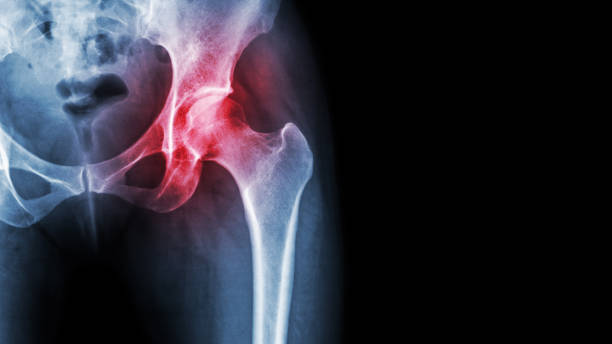

고관절 통증의 일반적인 원인 중 하나는 허리디스크입니다. 허리디스크는 허리 부위의 디스크에 문제가 생겨 발생하며, 이로 인해 통증을 겪게 됩니다. 하지만 모든 고관절 통증이 허리디스크로 연결되지는 않습니다. 고관절 주변에도 다양한 원인이 숨어 있을 수 있습니다.

고관절 통증은 종종 단일 원인뿐만 아니라 복합적인 문제에서 비롯됩니다. 이것이 진단과 치료를 어렵게 만들 수 있습니다. 예를 들어, 허리디스크와 함께 관절 주위의 염증, 근육 문제, 혹은 다른 구조적 문제가 동시에 발생할 수 있습니다.